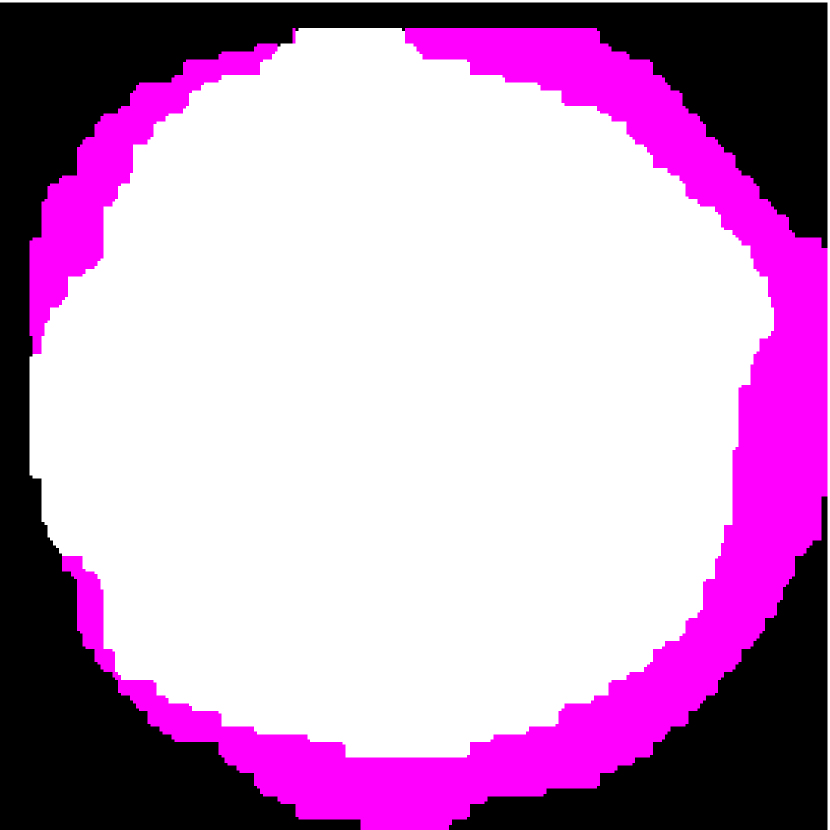

Figure 9: (a) The fusion of the binary segmentation maps by GC-LAE using different k𝑘k values. The region outside the LN-mask is in white. The blue, purple, and pink regions are detected as fat in one, two, and three segmentation results, respectively. (b) The LNP seeds are in white and the fat seeds are in pink. (c) The final NGC result based on the results of GC-LAE with global energy (i.e. using two rounds of GC-LAE). (d) The final NGC result based on the results of GC-LAE without global energy (i.e. using only one round of GC-LAE).

Figure 10: (a) Target HFU image. (b) Manual segmentation result. (c) The result of RFC+STS-LS. (d) The result of NGC with depth-dependent profiles. (e) The result of proposed method without global energy (one round of GC-LAE). (f) The result of proposed method with global energy (two rounds of GC-LAE).

NGC is used to refine the result of GC-LAE to guarantee the nested relationship among PBS, fat and LNP, and obtain the final segmentation result. As described in Sec. III-C2, we obtain depth-dependent PBS parameters IpTsubscriptsuperscript𝐼𝑇𝑝I^{T}_{p} and σpsubscript𝜎𝑝\sigma_{p} based on the GC-LAE segmentation result. We also generate seeds for the fat and LNP regions based on the previous segmentation result. NGC can correct the errors of GC-LAE such as the mislabeled “halo” voxels outside the fat shown in Figure 6(d) (indicated by the green arrow in Figure 6(e)). The final segmentation result of NGC is shown in Figure 6(f).

Initial seeds for the LNP and fat regions are obtained from the confident regions obtained by the second round GC-LAE (the bottom row of Figure 7). As shown in Figure 9(a), we first obtained a fused segmentation map from the GC-LAE results. The voxel values Tpsubscript𝑇𝑝T_{p} in black, blue, purple, and pink regions are 0, 1, 2, and 3, which are the number of times that each voxel is considered to be fat by the three segmentation results. The pink region is considered the confident fat region, and the black region is the confident LNP region. As can be seen, there are some “halo” pixels outside the pink region that are falsely considered as LNP. We apply a morphological opening to remove the halo region of confident LNP region and define the remaining region as the seeds of LNP. We also set confident fat region as seeds for the fat region. Furthermore, we remove any fat (pink) regions that are completely contained by LNP seeds through connectivity analysis, so that the fat seeds only lie on the outer boundary of the LN-mask. As shown in Figure 9(b), pink pixels are the final seeds for fat, and the white pixels are the seeds for LNP.

For fat-PBS boundary, we do not change the edge cost, so NGC cuts the fat-PBS boundary by the intensity and the new depth-dependent PBS threshold obtained in Sec. III-C2. Figure 9(c) and (d) compares the result of NGC based on the segmentation results of GC-LAE with and without global energy. The result based on GC-LAE with global energy obtained more accurate LNP-fat boundary on the left.